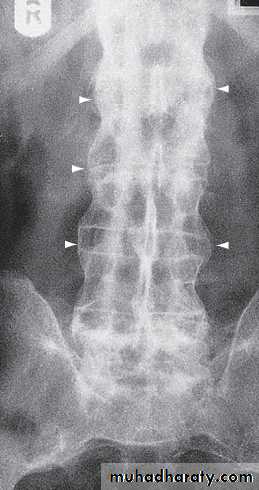

In established AS, radiographs of the sacroiliac joint show irregularity and loss of cortical margins, widening of the joint space and subsequently sclerosis, joint space narrowing and fusion.Lateral thoracolumbar spine Xrays may show anterior ‘squaring’ of vertebrae due to erosion and sclerosis of the anterior corners and periostitis of the waist.

In advanced disease, ossification of the anterior longitudinal ligament and facet joint fusion may also be visible. The combination of these features may result in the typical ‘bamboo’ spine.Erosive changes may be seen in the symphysis pubis, the ischial tuberosities and peripheral joints.

Patients with early disease can have normal Xrays, and if clinical suspicion is high, MRI should be performed. This is much more sensitive for detection of early sacroiliitis than Xray and can also detect inflammatory changes in the lumbar spine.